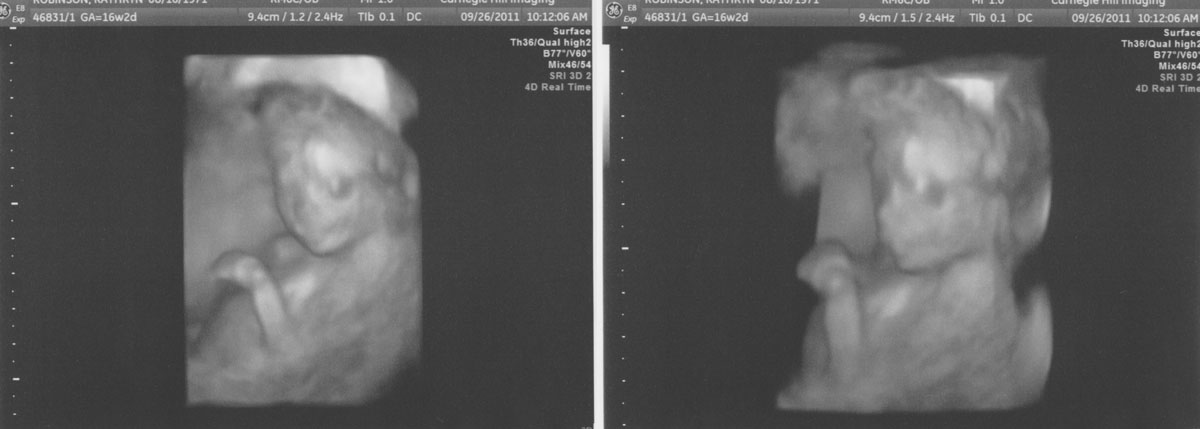

16 Weeks (3D Imaging!)